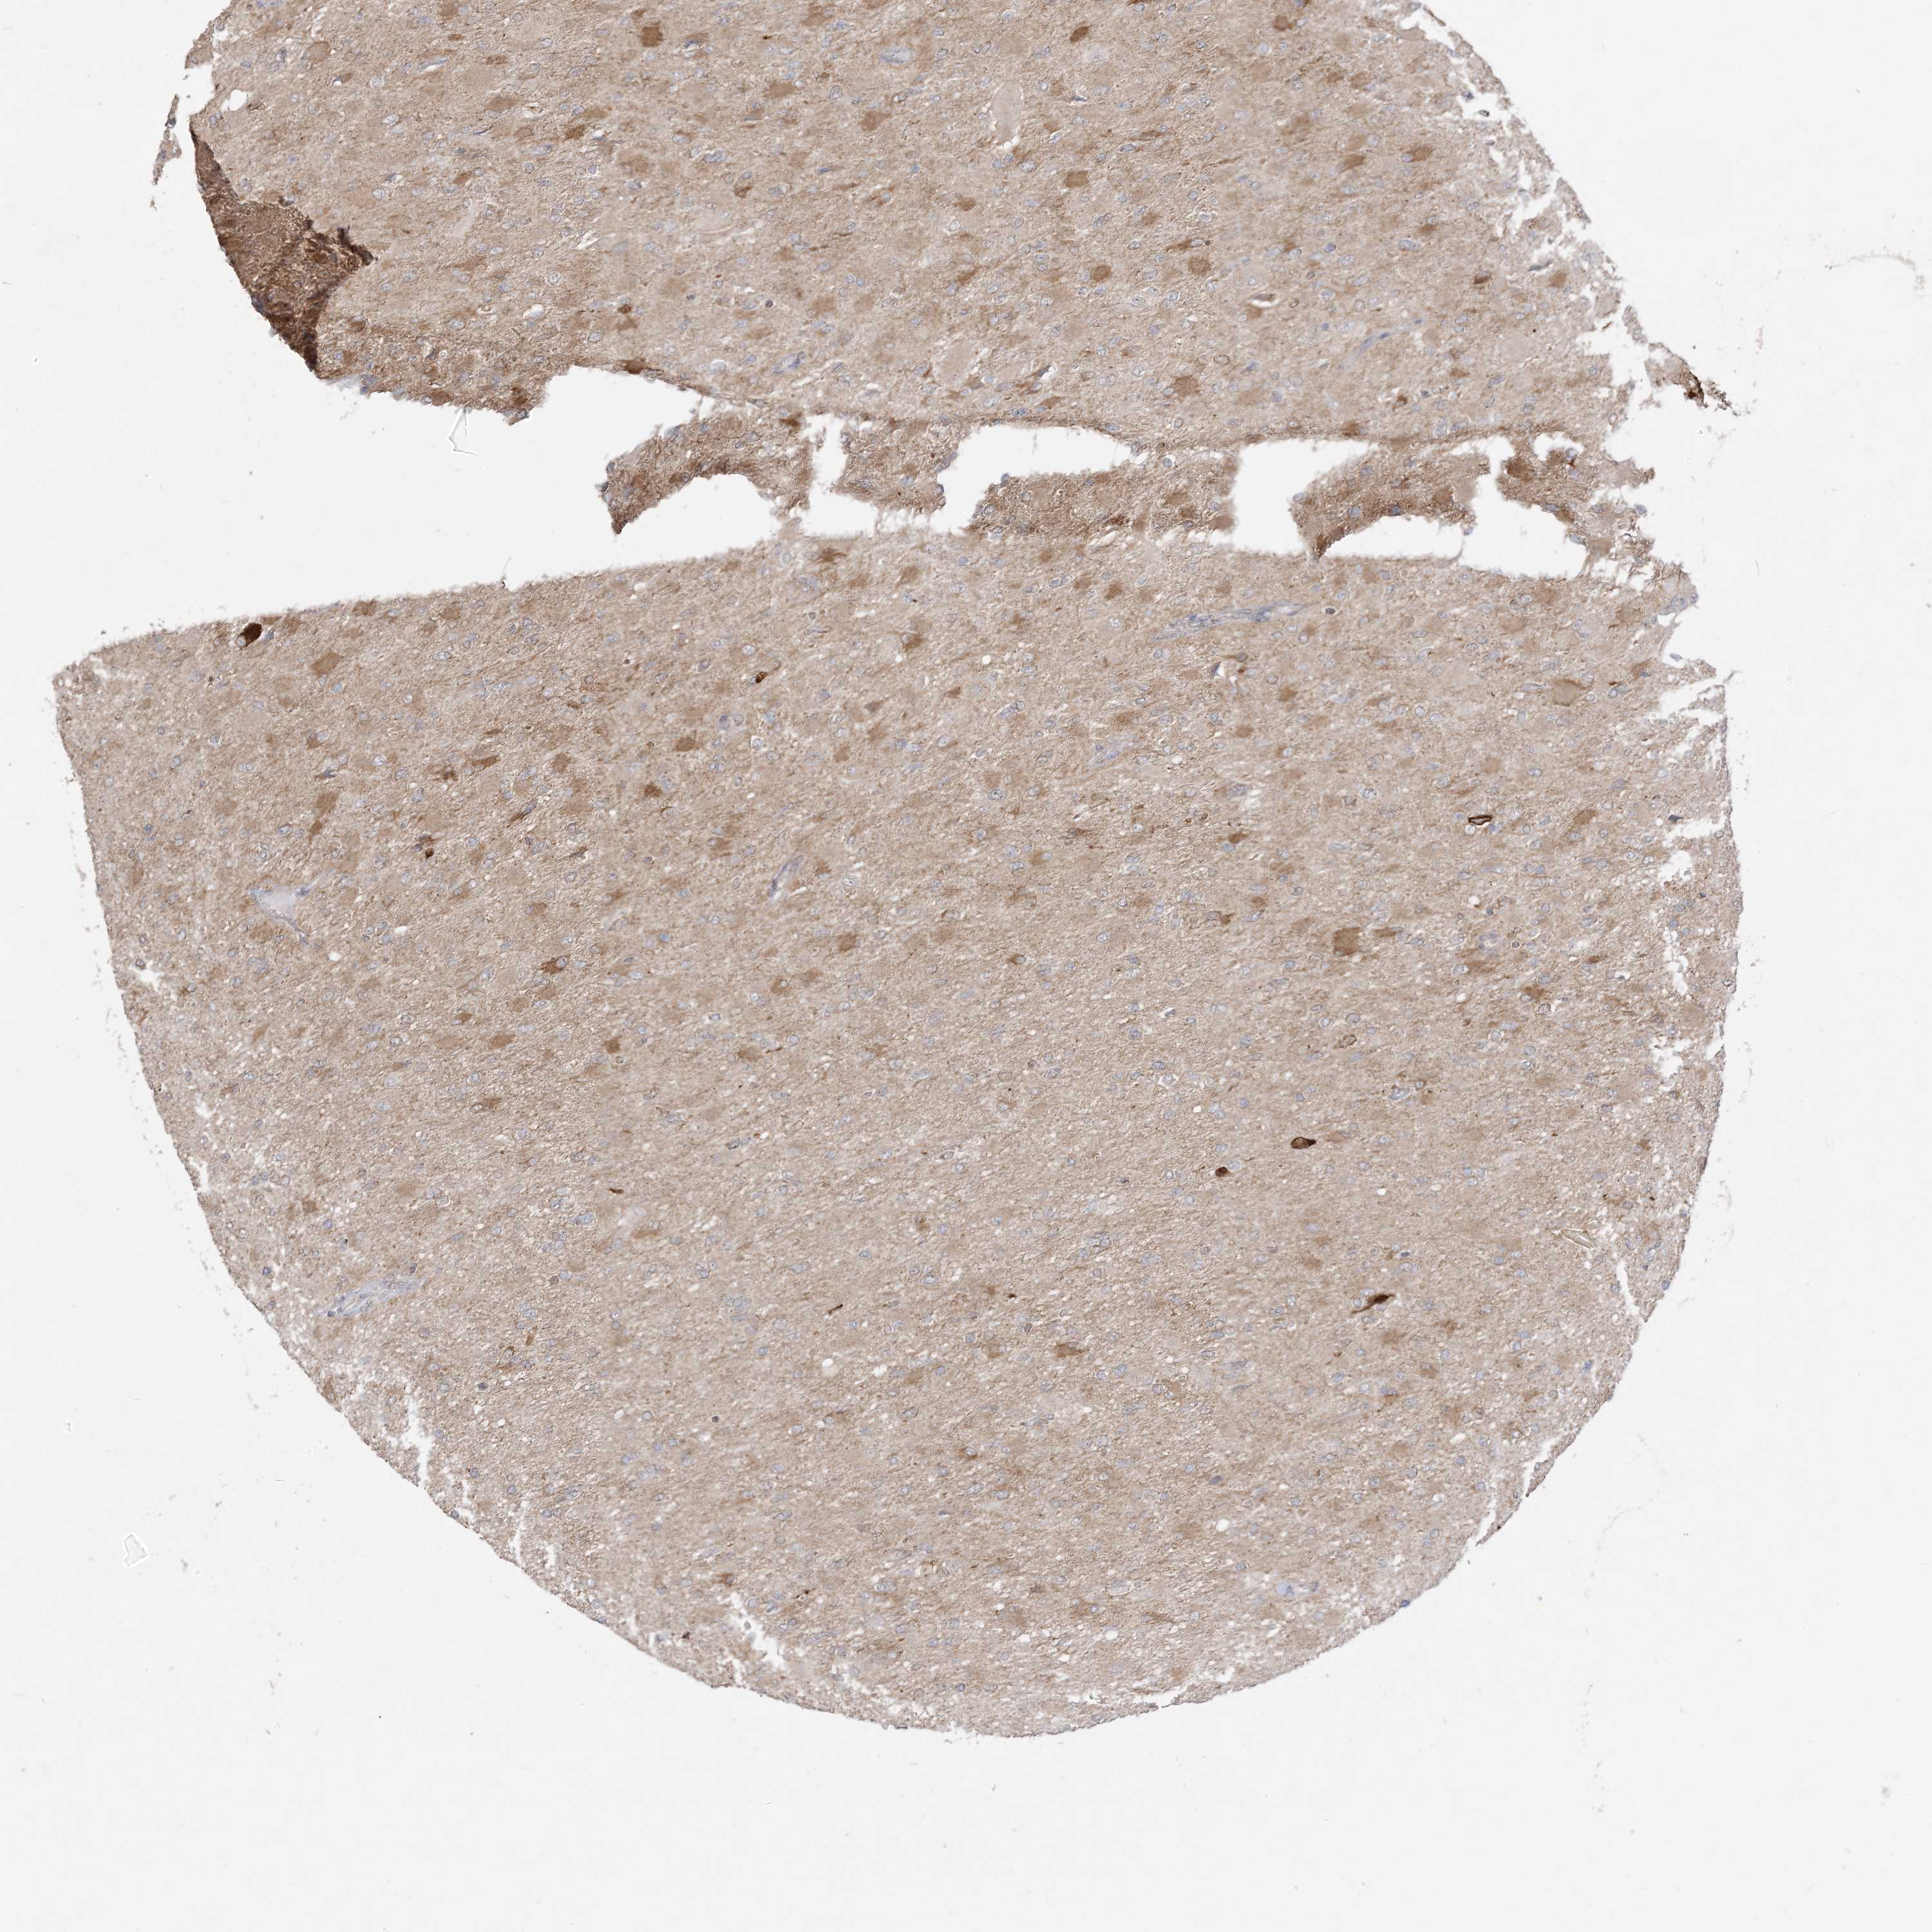

GLIOMA - Protein expressioni

A mouse-over function shows sample information and annotation data. Click on an image to view it in a full screen mode. Samples can be filtered based on level of antibody staining by selecting one or several of the following categories: high, medium, low and not detected. The assay and annotation is described here.

Note that samples used for immunohistochemistry by the Human Protein Atlas do not correspond to samples in the TCGA dataset.

Antibody stainingi

Antibody staining in the annotated cell types in the current human tissue is reported as not detected, low, medium, or high, based on conventional immunohistochemistry profiling in selected tissues. This score is based on the combination of the staining intensity and fraction of stained cells.

Each image is clickable and will lead to virtual microscopy that enables deeper exploration of all samples and also displays staining intensity scores, fraction scores and subcellular localization as well as patient and tissue information for each sample.

Antibody CAB037142

Staining

High

Medium

Low

Not detected

Intensity

Strong

Moderate

Weak

Negative

Quantity

>75%

75%-25%

<25%

None

Location

Nuclear

Cytoplasmic/membranous

Cytoplasmic/membranous,nuclear

Glioma, malignant, High grade

Glioma, malignant, Low grade